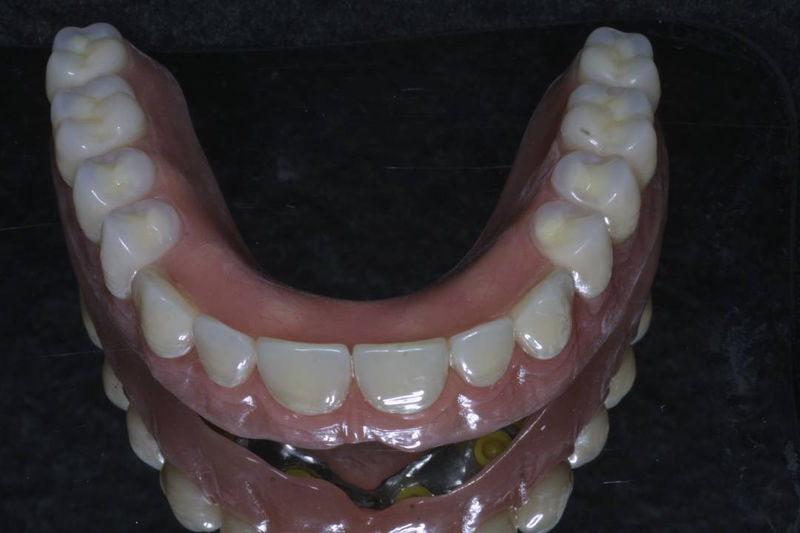

Restauraciones fabricadas en el laboratorio los cuales se usan para reemplazar dientes ausentes en toda una arcada usando implantes y/o tejidos blandos como soporte y que pueden y deben de ser removidas para su limpieza. Para poder enviar el caso al laboratorio se toman impresiones utilizando materiales de impresión o técnicas modernas digitales.